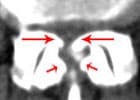

Es liegt eine krankhafte Verengung des Wirbelkanales vor (Stenose des Spinalkanales). Diese tritt in der Regel erst in höherem Alter auf. Sie wird verursacht durch:

• eine sich breitbasig vorwölbende Bandscheibe

• eine Verdickung des Bandapparates, welcher den Wirbelkanal auskleidet

• Verschleiß von Wirbeln und Wirbelgelenken, die knöcherne Anbauten entwickeln, welche in den Wirbelkanal hineinragen

Menschen, die bereits angeboren einen relativ engen Spinalkanal haben, sind für die Entwicklung dieser Erkrankung besonders anfällig.